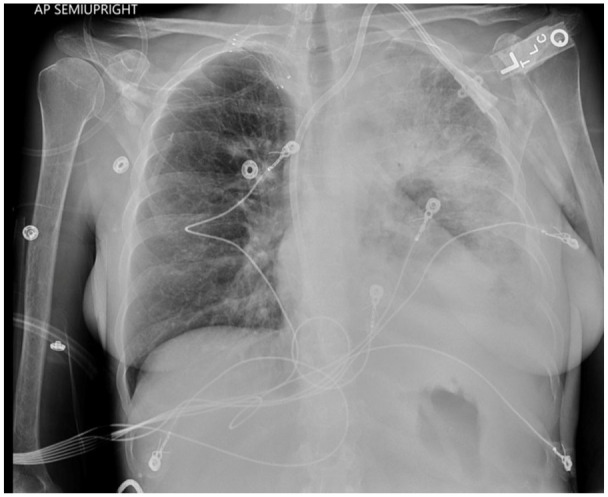

Blastomycosis is a systemic fungal infection caused by Blastomyces dermatitidis, primarily found in the Ohio and Mississippi River valleys. It often presents nonspecific symptoms, and while pulmonary involvement is common, progression to acute respiratory distress syndrome (ARDS) is rare but severe. This report examines a 55-year-old female patient with multiple comorbidities who developed ARDS due to blastomycosis. Imaging revealed multilobar infiltrates and pleural effusion, with cultures confirming blastomycosis. Despite broad-spectrum antibiotics and antifungal therapy, a delayed diagnosis led to respiratory failure and death. The case emphasizes the diagnostic challenges of blastomycosis, which can mimic conditions like bacterial pneumonia and malignancy. Treatment with amphotericin B is crucial for severe cases, but delays in diagnosis can worsen outcomes. This highlights the necessity for prompt diagnosis and comprehensive management, including early recognition of fungal infections in critically ill patients.